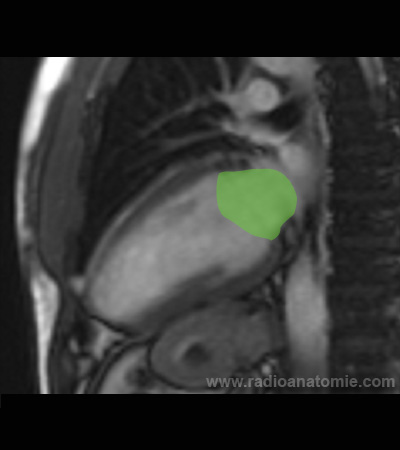

Radioanatomie et plans de coupe en IRM cardiaque

Coupe long axe 2 cavités

Oreillette gauche